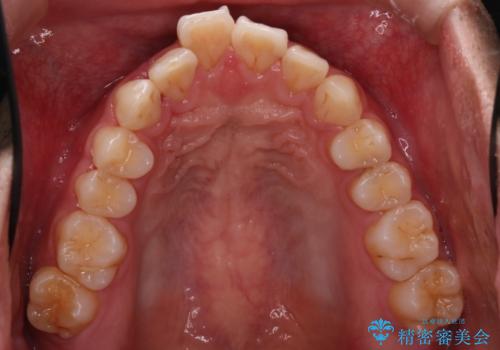

- 前歯が出ていることを主訴に来院されました。

歯列の幅が狭かったため、横に広げながらスペースを作り、叢生の改善を行いました。

左側の犬歯関係も治療前より良い状態で治療を完了することができました。

今回は臼歯部の遠心移動を行うために2級ゴムを使用しています。